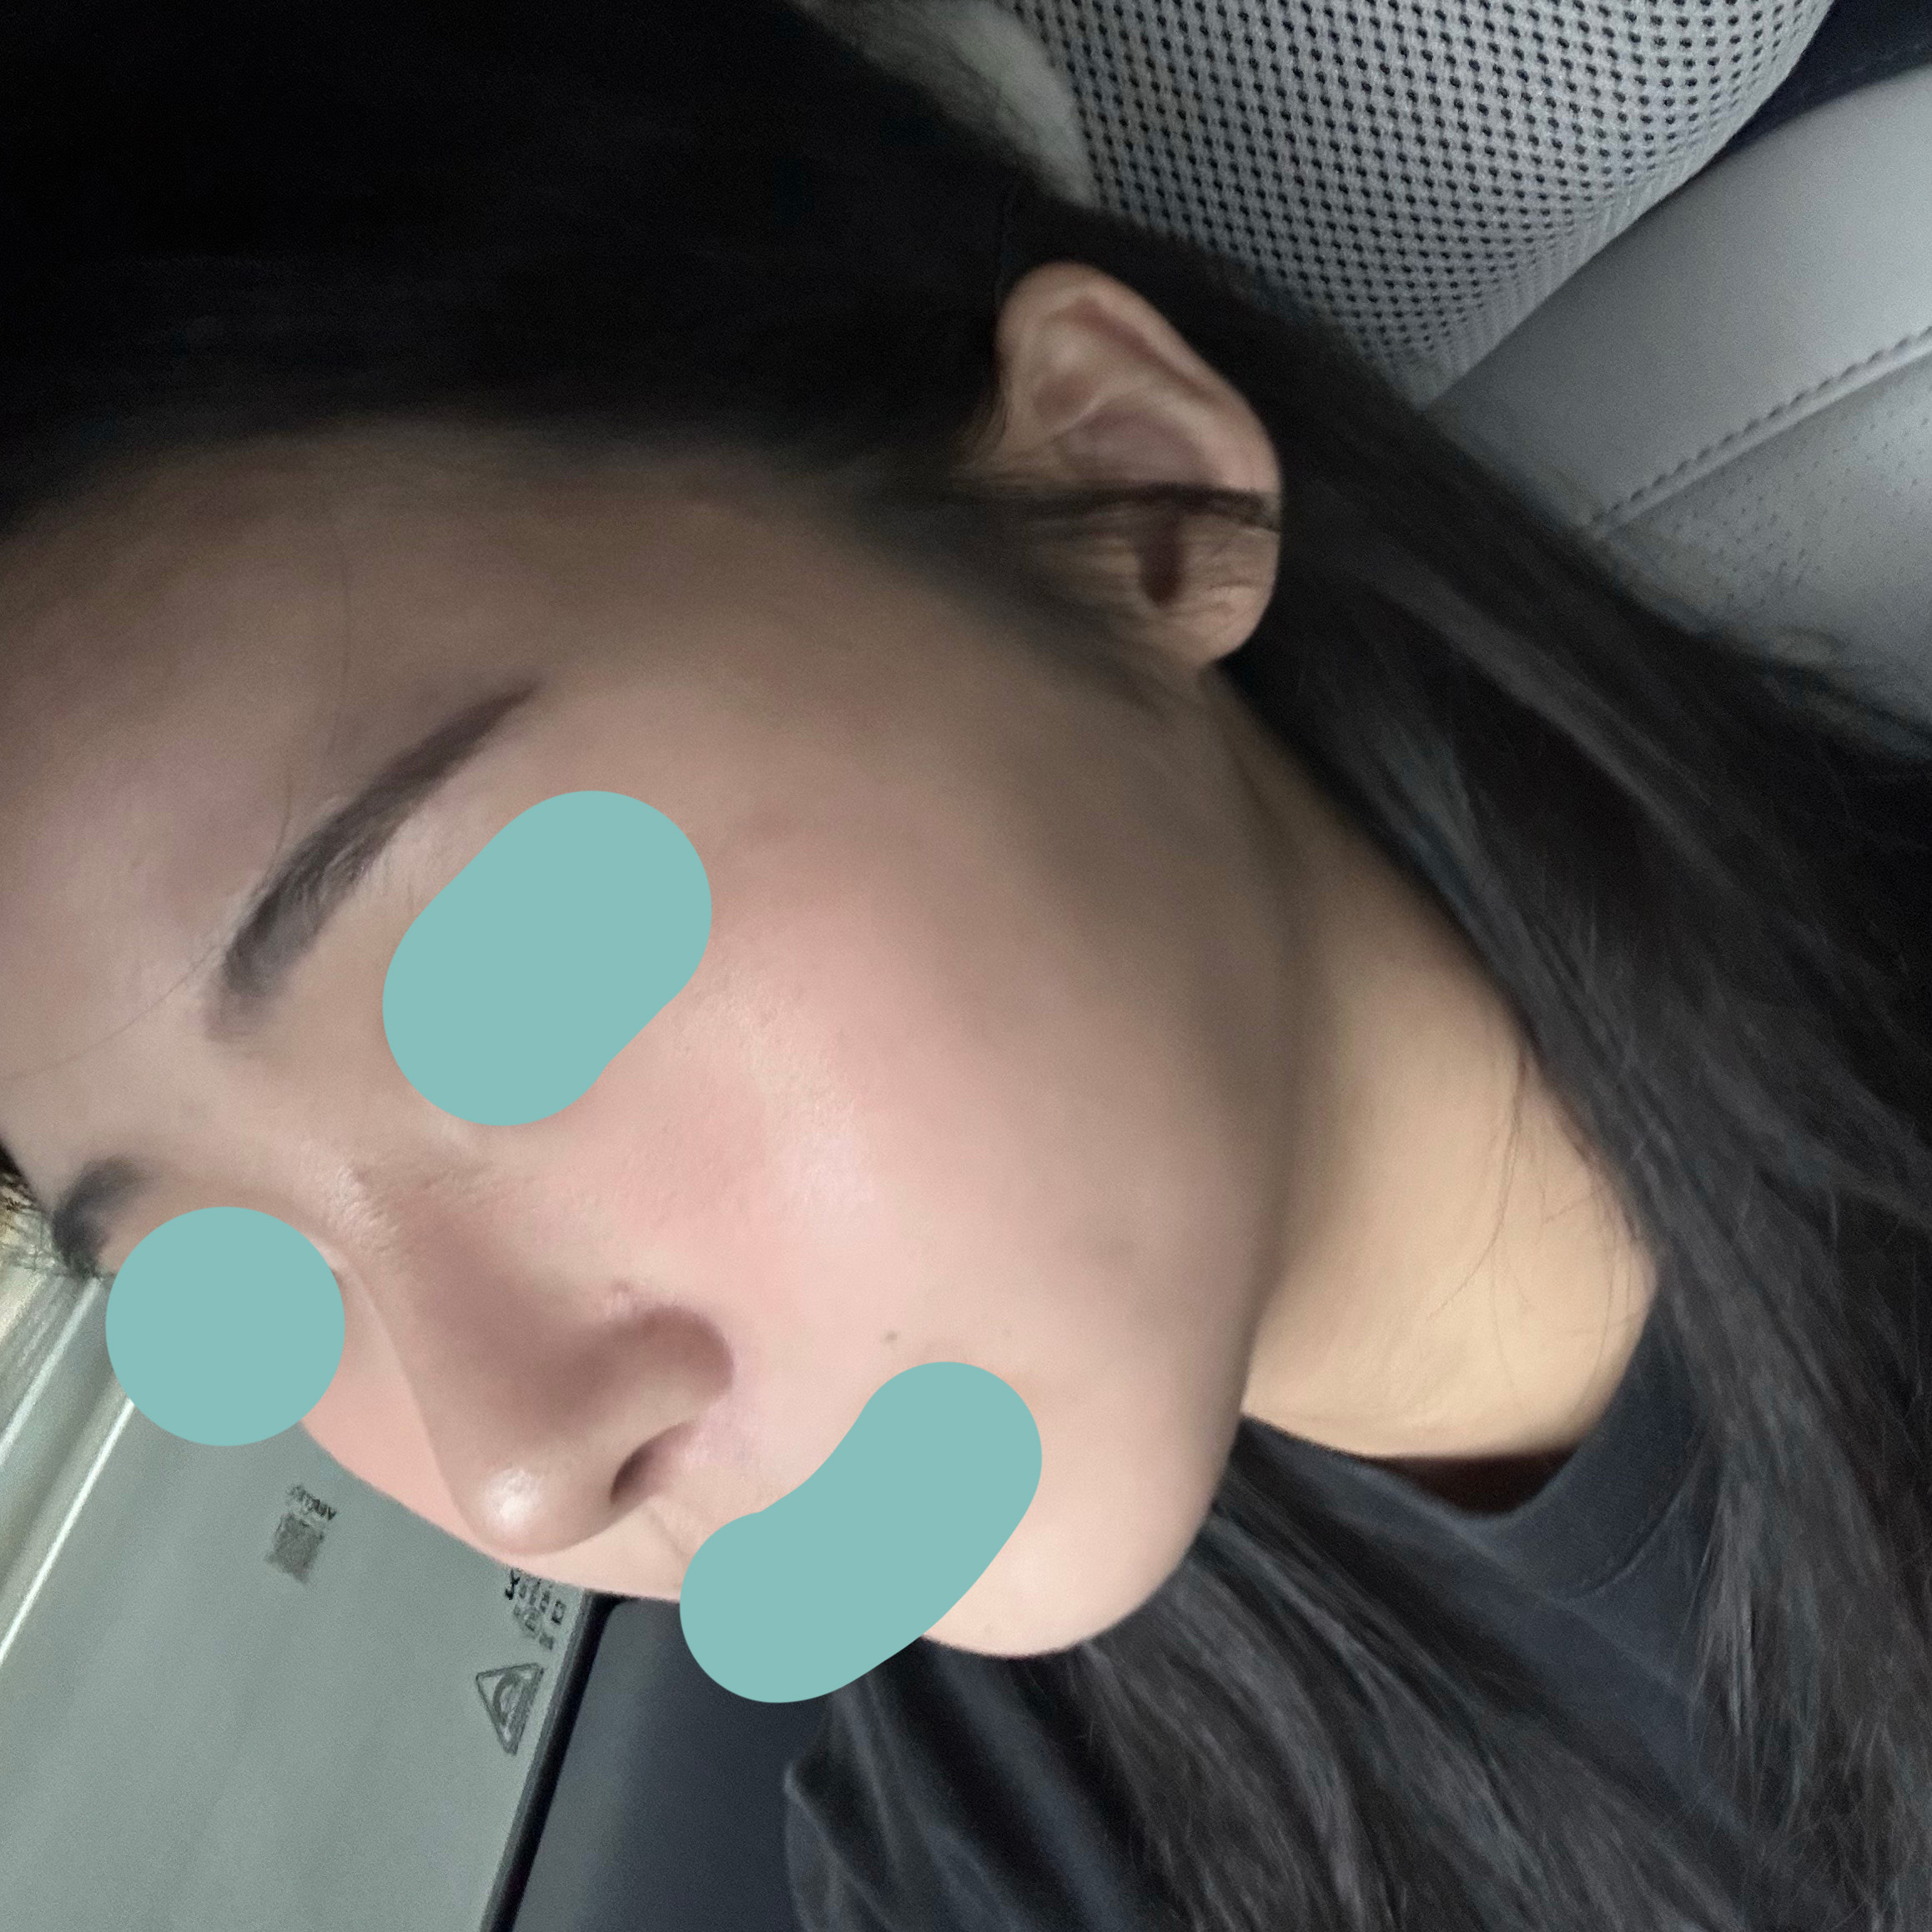

코수술받고 3주차됐어용

저는 12월 6일에 바이브 성형외과에서

코수술을 받았고 지금은 3주차가 되었습니다.

실리콘, 비중격, 귀연골, 기증늑연골사용해서

수술했고 이물질제거와 복코, 용코교정한지

3주차 됐는데요

벌써부터 너무 자연스럽고

평소 고민이었던 용코도 정말 많이 교정되고

자연스럽고 화려한 코라인이 나와서

주변에서 칭찬 많이 받고 저도 너무 만족스럽고

바이브 성형외과에서 수술받기 너무 잘했다는

생각이 들어요~!